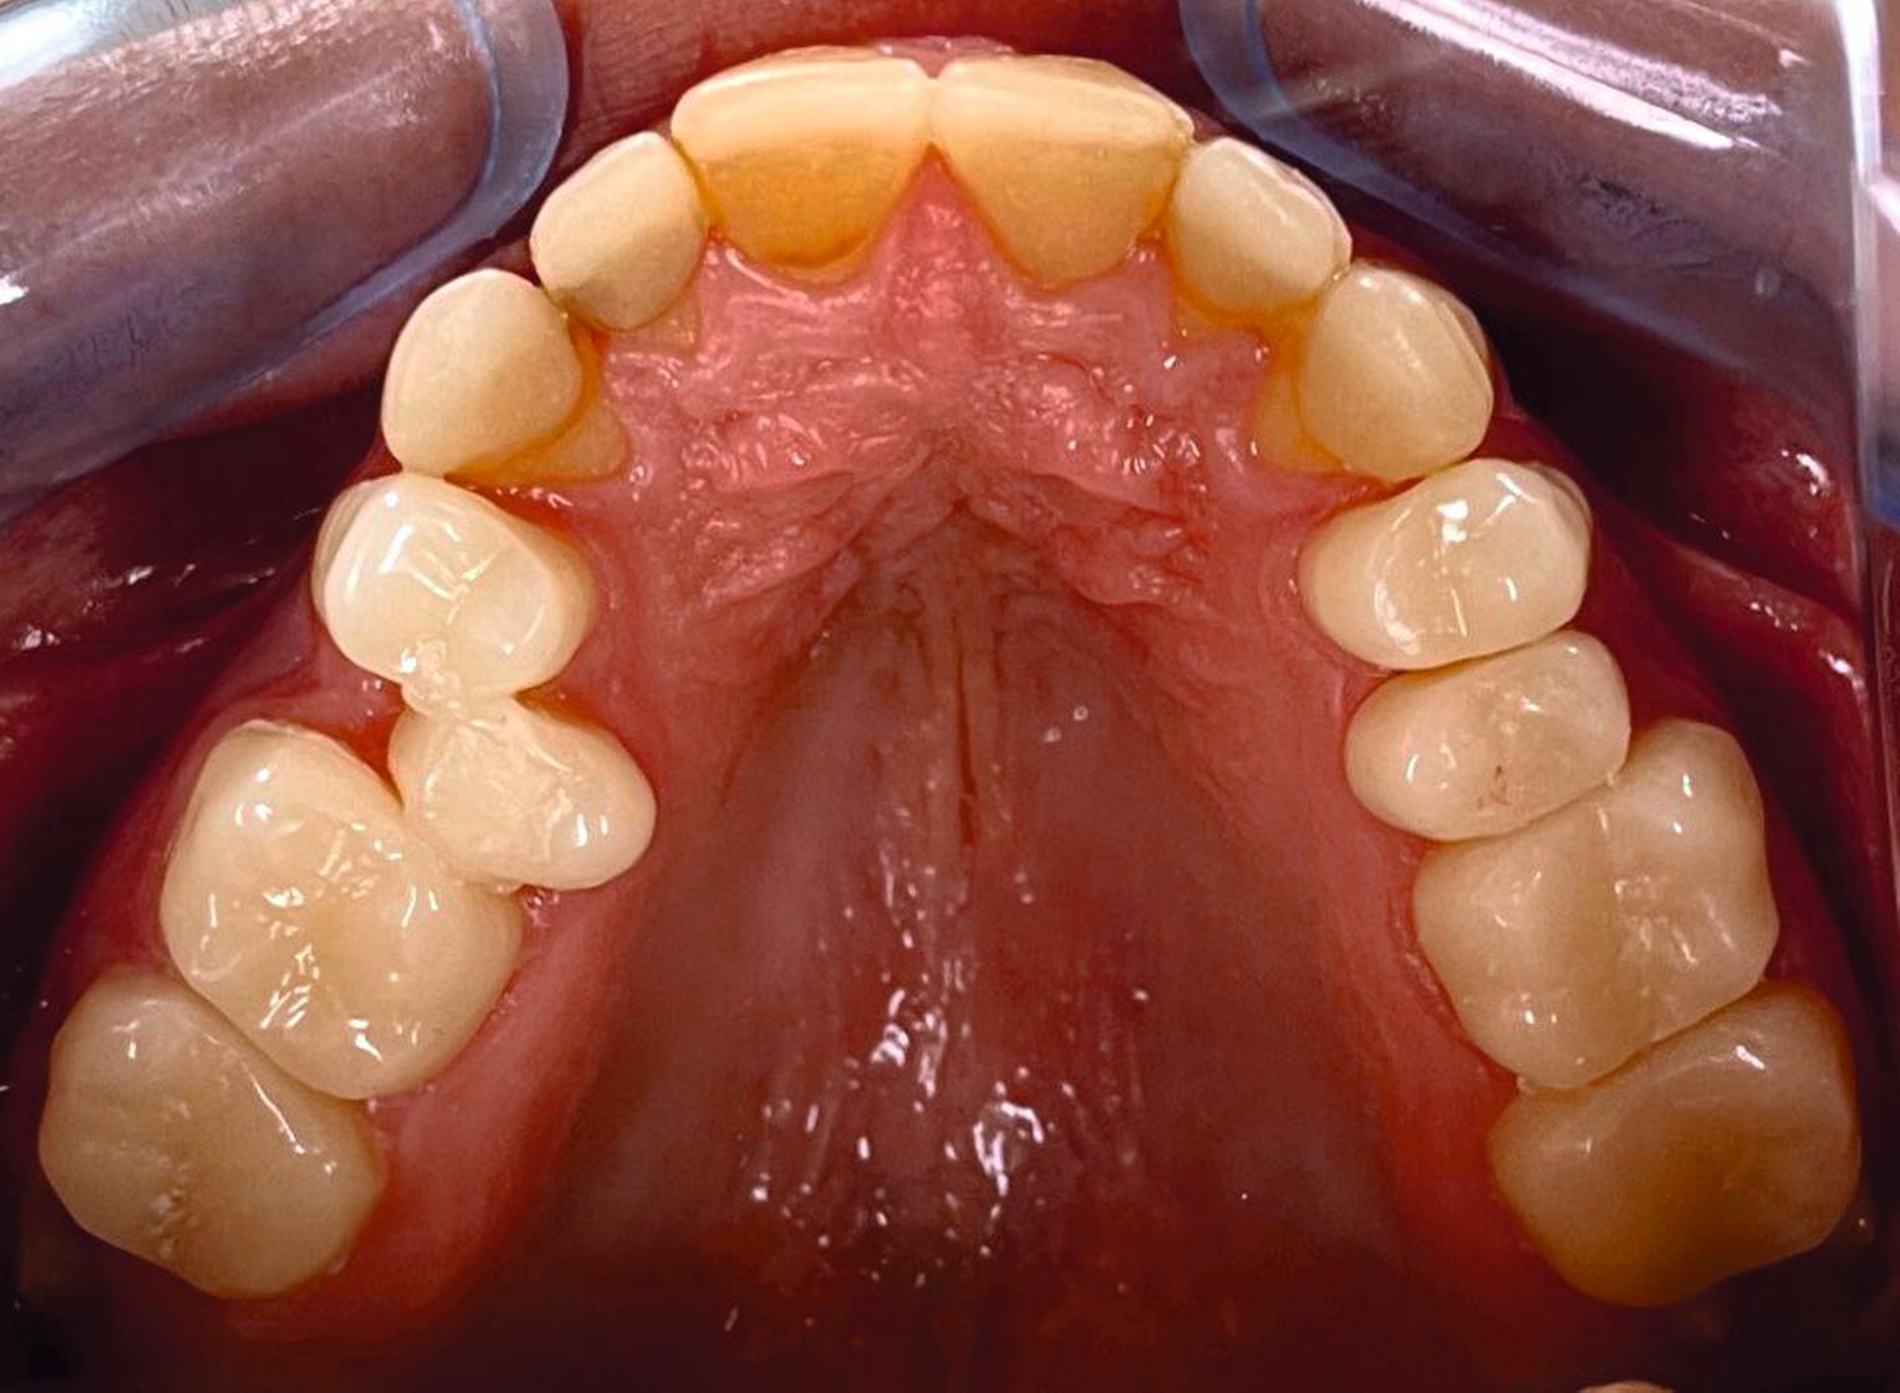

Klinisch zeigten sich ein nicht-kariöses Wechselgebiss mit generalisierter Schmelzhypoplasie an allen Zähnen sowie eine insuffiziente Mundhygiene. Zusätzlich bestanden eine fehlende Mittellinienübereinstimmung, ein Overbite von minus vier Millimetern und ein Overjet von sechs Millimetern (Abbildung 5), die sich phonetisch in einem interdentalen Sigmatismus äußerten. Röntgenologisch waren alle Zähne angelegt, jedoch war der Zahnschmelz stark reduziert oder vollständig fehlend (Abbildung 6).

Die restaurative Versorgung erfolgte in zwei Phasen: Die Frontzähne wurden im Jahr 2018 (Abbildungen 7 und 8), die Seitenzähne im Jahr 2023 behandelt (Abbildungen 9 bis 12). Im Jahr 2018 fiel die Therapieentscheidung auf indirekte Restaurationen, da eine mangelnde Adhärenz des Patienten vorlag, die sich in geringer Geduld für längere Sitzungen äußerte. Zudem war über einen längeren Zeitraum keine zuverlässige Trockenlegung möglich. Durch diese Vorgehensweise konnten die Anzahl und die Dauer der Behandlungstermine reduziert werden.